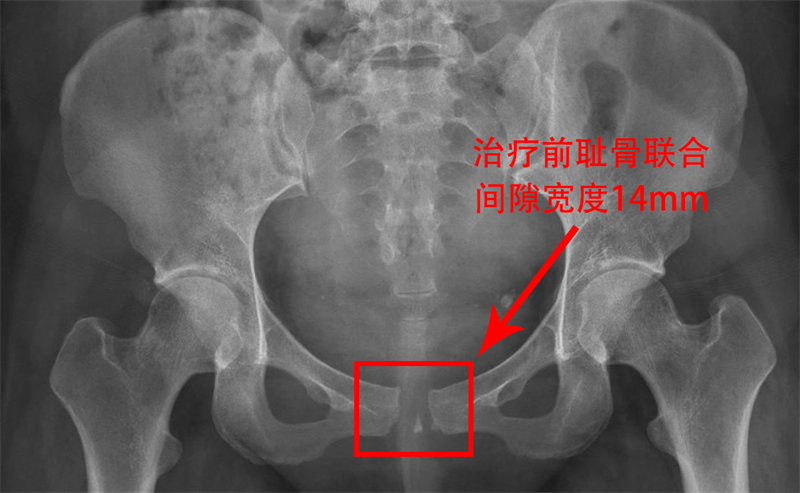

今年年初,剛經歷分娩的麥女士在產后7天時,因恥骨區域劇烈疼痛,連簡單的翻身、屈腿都變得異常艱難,更不用說正常行走了。在家人的陪同下,她坐著輪椅來到了柳人醫盆底康復治療區就診。經過醫生詳細詢問病史和查體,結合骨盆X光檢查結果,麥女士被明確診斷為恥骨聯合分離,分離程度達到了14mm。

恥骨聯合分離,這個聽起來有些陌生的名詞,實際上在孕產婦中并不罕見。正常恥骨聯合間距為4-5mm,妊娠期婦女生理性增寬3-7mm,而當分離程度>10mm時,即可診斷為恥骨聯合分離。患者往往會出現恥骨聯合、腹股溝區疼痛,活動受限,甚至出現搖擺步態。雖然其發生率僅為1/300-1/30000,但一旦發生,卻會給寶媽們帶來極大的痛苦和不便。

令人欣喜的是,經過5次治療,麥女士的疼痛基本消失,行走自如,無搖擺步態。治療后4月余復查骨盆X光顯示,恥骨聯合已經無分離,且沒有出現反彈的情況。麥女士終于恢復了往日的活力,重新擁抱了健康的生活。